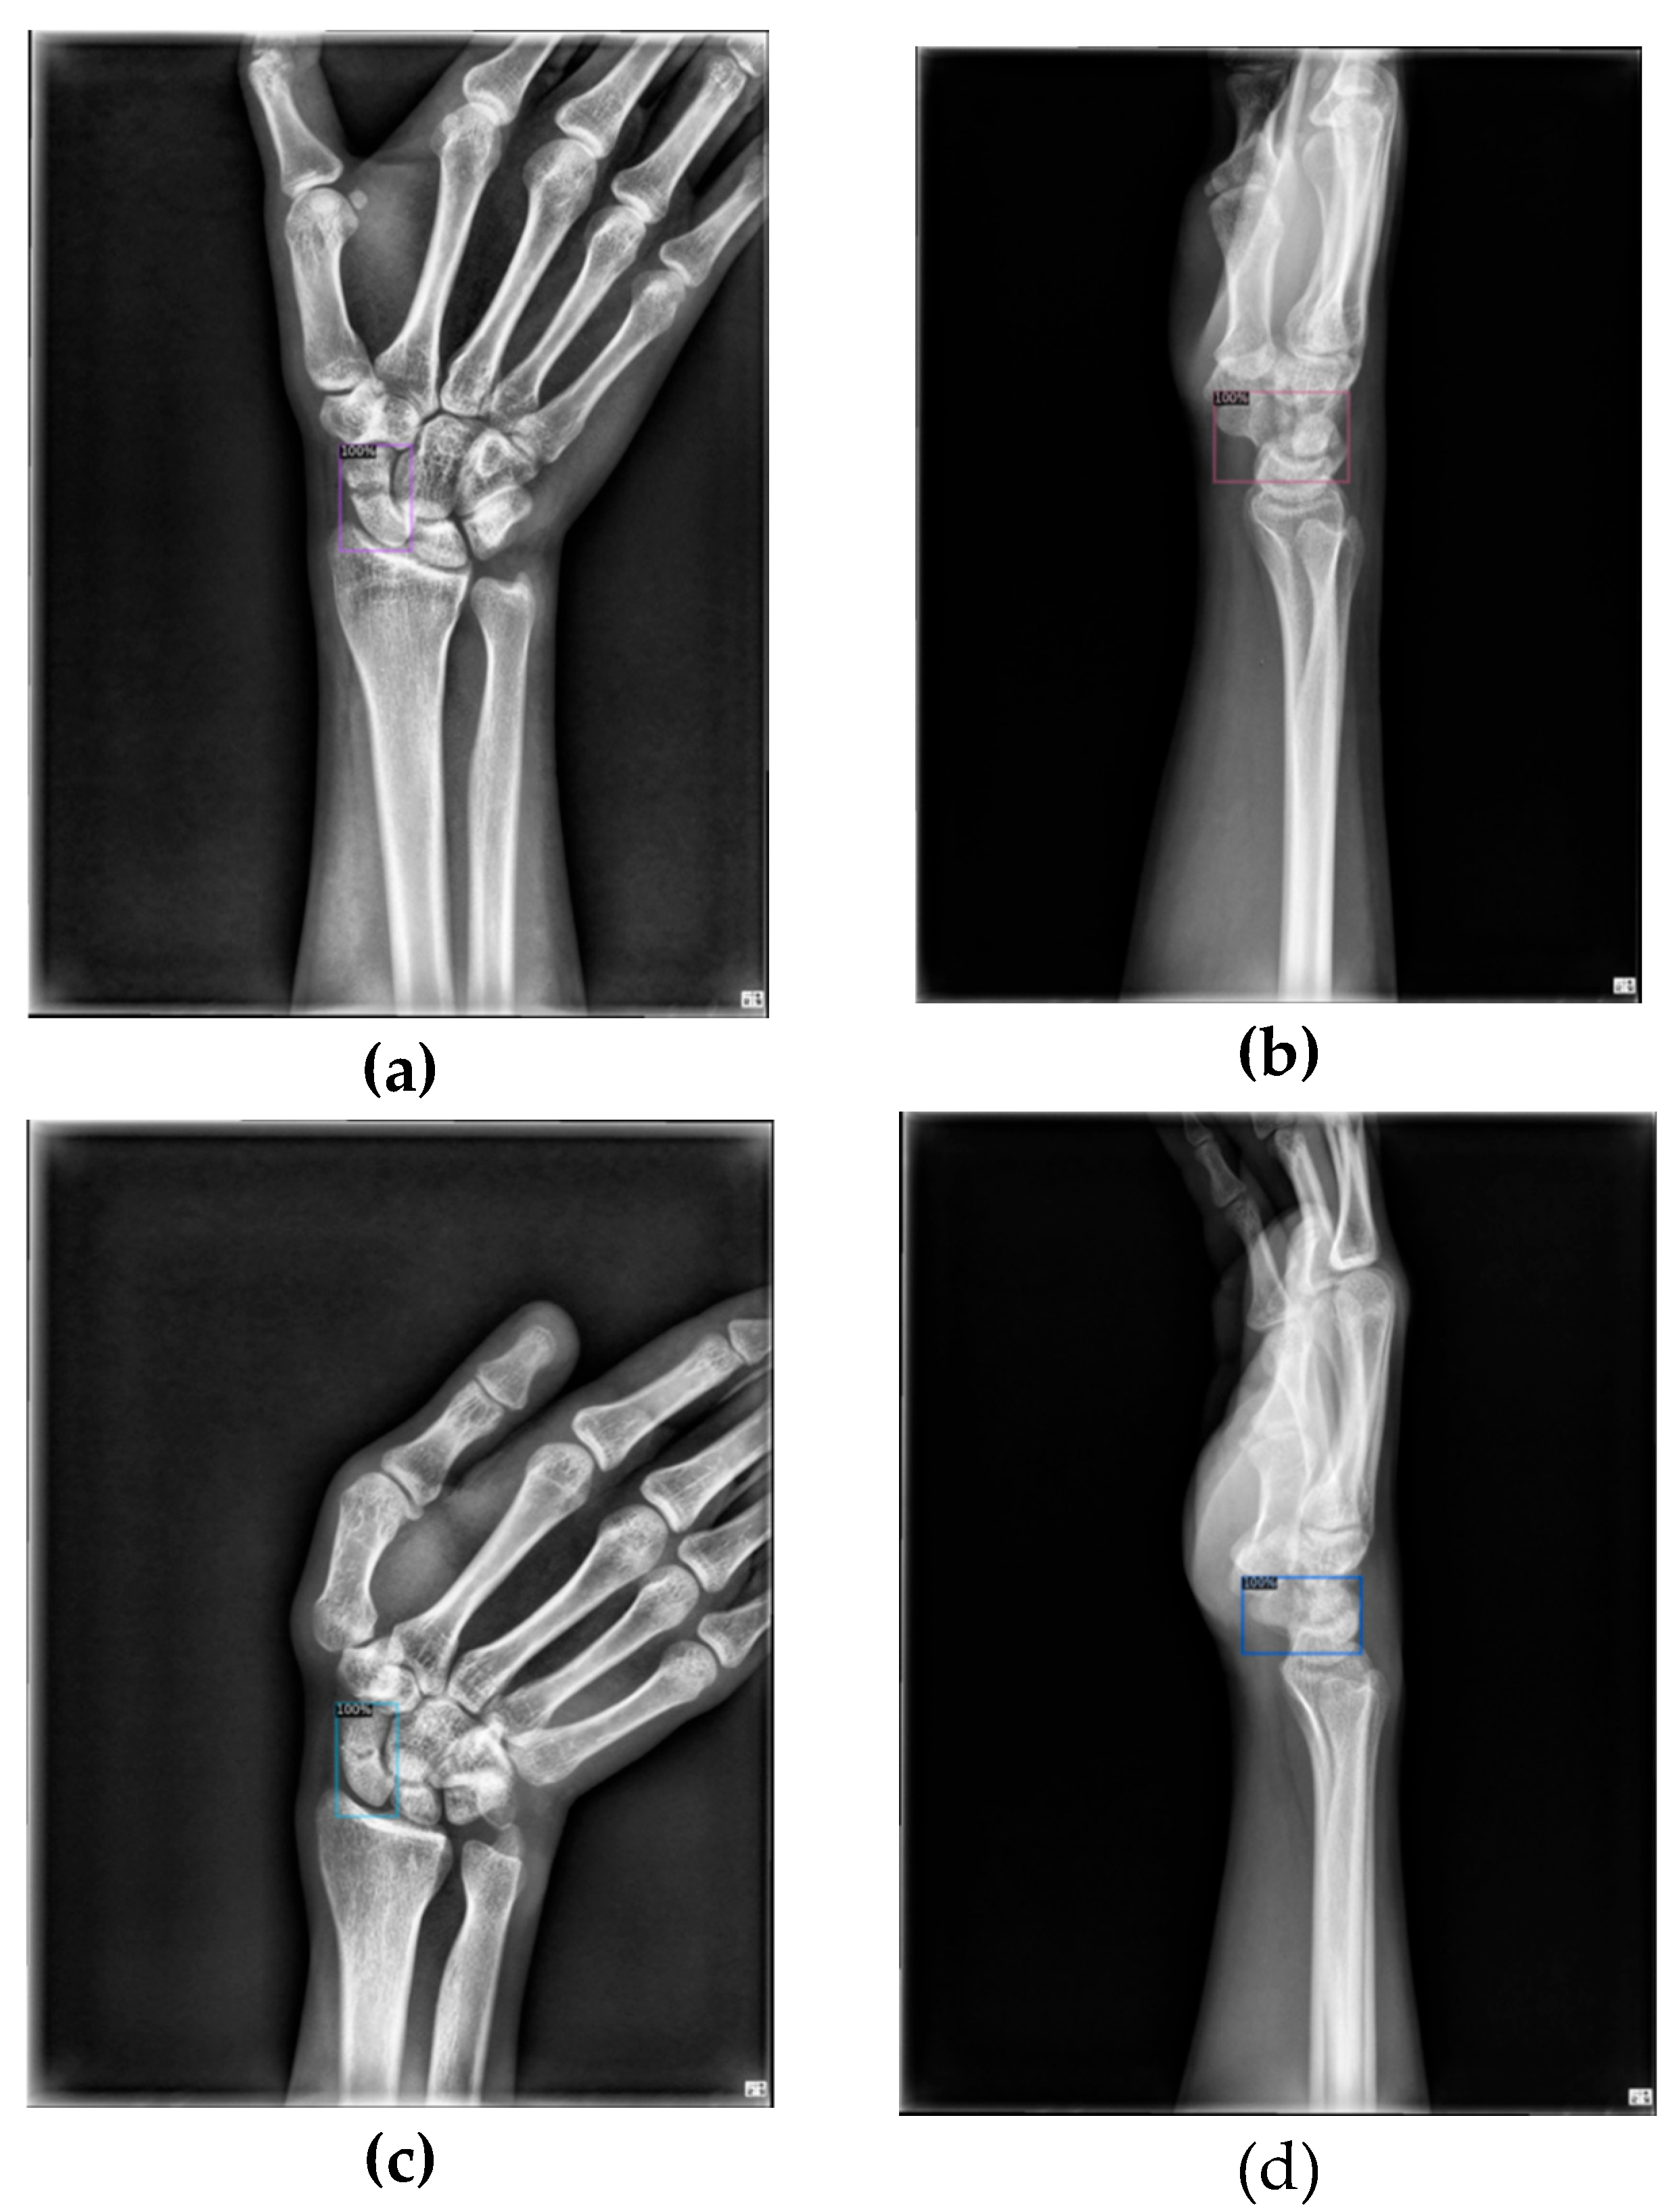

The main objective of this article is to locate the scaphoid bone in X-ray images and assist doctors in determining whether it is fractured, as well as in identifying the fracture area. Displaced fractures are typically easy to detect in X-ray images, allowing doctors to quickly diagnose them. In contrast, non-displaced and occult fractures are more challenging to identify due to X-ray projection shadowing and variations in bone density among patients. Additionally, discrepancies in interpretation between radiologists and orthopedic surgeons are common. For fractures not visible in the anterior-posterior view, doctors must examine the scaphoid bone for discontinuities, making the diagnosis time-consuming and demanding a thorough understanding of the scaphoid.

As mentioned earlier, the first stage aims to extract the scaphoid bone from the entire wrist X-ray image. For this purpose, we use the Faster R-CNN model combined with a Feature Pyramid Network (FPN). Faster R-CNN is a renowned two-stage detector that incorporates a Region Proposal Network (RPN), which enhances the speed of the detector by replacing the traditional algorithmic approach used in the initial stage. The Feature Pyramid Network improves the utilization of feature maps at various scales, addressing the issue that deeper networks might lose small objects.

In our research, if the first stage fails to accurately locate the scaphoid bone, subsequent fracture detection cannot proceed effectively. Therefore, we employ the two-stage Faster R-CNN model with FPN at this stage, despite its slightly slower processing time, due to its improved accuracy. Unlike the original Faster R-CNN model, which uses a single-level feature map to generate candidate boxes, the FPN integrates feature maps from multiple levels. This approach helps retain small objects that might otherwise be lost during pooling, thereby enhancing detection performance for small and medium-sized objects.

Considering that a typical wrist X-ray image measures approximately 2000 × 1600 pixels and the scaphoid bone region is around 150 × 150 pixels, the scaphoid falls into the category of small and medium-sized objects. To address this, we use the Feature Pyramid Network (FPN) which upsamples and enlarges deep features to match the size of previous layers, then integrates them using a convolutional layer. Specifically, after incorporating the FPN, a 1×1 convolutional layer adjusts the channel number to 256, and deep features are upsampled and combined with the previous layer’s features. A final 3×3 convolutional layer refines the feature map. This multi-layer approach, with varied anchor box sizes and aspect ratios, enhances overall detection performance.